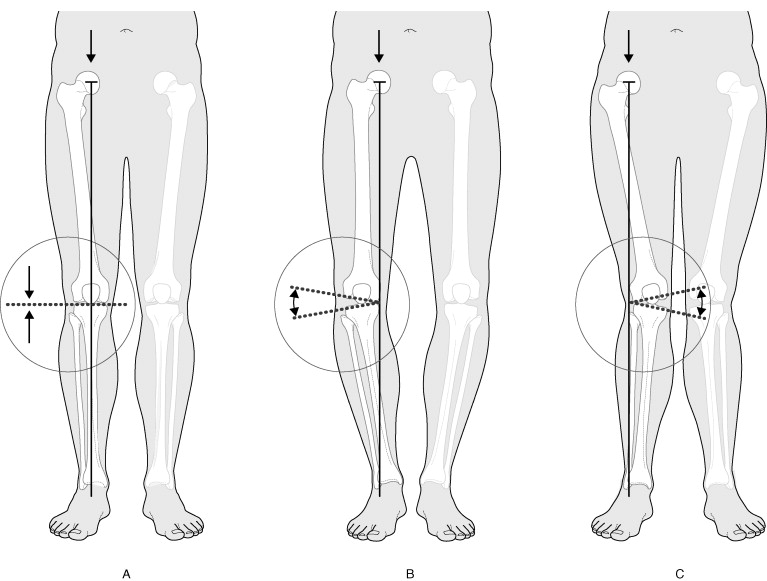

- genoux en varus ou valgus,

Les triathlètes ayant un passé de nageurs ont normalement peu de force au niveau des abducteurs de hanche (moyen fessier) ainsi que les triathlètes fatigués après la partie cycliste, ce qui a pour conséquence d’augmenter l’adduction de la cuisse et une rotation interne durant la phase intermédiaire (réception du pied au sol). C’est le genou qui en ressort perdant avec un accroissement du valgus (genoux vers l’intérieur d’une ligne médiane).

Parfois, cette bourse peut devenir enflammée. Cette condition peut être une manifestation d’une blessure, résultant souvent d’une utilisation excessive. Les causes de bursite trochantérienne comprennent la longueur inégale des jambes, le syndrome de la bande iliotibiale et la faiblesse des muscles abducteurs de la hanche et une inflammation des tendons des muscles fessiers.